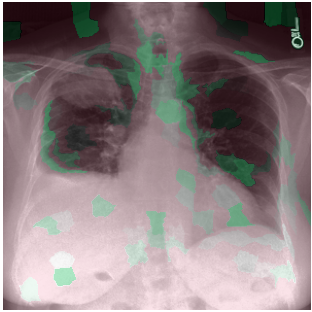

3.3 Interpretability

Post-Hoc Comparisons. We compare our concept-based explanations to post-hoc XAI techniques LIME and SHAP, applied to the baseline InceptionV3 model. The image explanations generated by these techniques disagree with each other and the medical ground truth. We show an example of this observation in Figure 7, where both techniques fail to capture the large mass in the X-ray, and highlight irrelevant regions such as areas outside of the lung as incorrectly important to the classification decision. In contrast, our approach correctly identifies the presence of a mass. More examples are shown in Figure 10.

Refer to caption

(a) Ground Truth

(b) LIME

(c) SHAP

(d) CXR-LLaVA Generated Report

(e) Our Approach

Figure 7: Example of our explanation approach outperforming LIME, SHAP and CXR-LLaVA. Ground truth (a) is a “Large right upper zone mass". LIME (b) and SHAP (c) fail to capture the mass in the X-ray. Most important image regions are bounded by yellow for LIME, and shown in more vibrant green for SHAP. CXR-LLaVA (d) generates a report which wrongly describes the image as non-cancerous. Our approach (e) correctly identifies the presence of a mass.